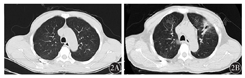

例3,男性,59岁,以发热10 d为主诉于2017年7月22日入我院。患者10 d前无明显诱因出现发热,最高体温38.5 ℃。入院后查胸部CT示双肺多发结节,真菌感染待排除,细菌感染不排除(图2A);查血常规示WBC 0.62×109/L、中性粒细胞计数(NEUT)0.17×109/L、Hb 58 g/L、Plt 48×109/L;凝血示血浆凝血酶原时间(PT)11.4 s,活化部分凝血活酶时间(APTT)27.6 s,纤维蛋白原(FIB)3.98 g/L,血浆凝血酶时间(TT)14.7 s,D-二聚体280 ng/ml;骨髓涂片示:异常早幼粒细胞0.835。结合流式细胞学、染色体、融合基因等检测结果确诊为急性早幼粒细胞白血病(APL)。予全反式维甲酸(ATRA)每天20 mg/m2+去甲氧柔红霉素(IDA)每天8 mg/m2,第2、4、6天+三氧化二砷(ATO)每天0.16 mg/kg,广谱抗生素联合伏立康唑抗感染治疗,患者胸痛、胸闷症状进行性加重,2017年8月5日复查CT示左肺上叶新发高密度影,反晕征,真菌感染(毛霉菌不除外),建议行肺穿刺活组织检查,伴有左侧胸腔积液。遂改用AmB抗真菌治疗,起始剂量为每天0.5 mg/kg,逐渐增大至最大耐受剂量,并密切监测不良反应。2017年8月7日行CT引导下肺穿刺活组织检查。1周后肺活组织培养考虑毛霉菌感染,因患者无法耐受AmB,改为泊沙康唑200 mg/6 h口服。2017年8月15日CT示疾病较前进展,双肺感染并左肺上叶空洞形成,双肺磨玻璃影增多,左侧胸腔积液增多并左下肺膨胀不全,右侧胸腔少量积液,加用利奈唑胺覆盖G+球菌,加用AmB雾化吸入抗真菌治疗。2017年8月24日CT示双肺感染并左肺上叶空洞形成较前好转。2017年9月3日患者骨髓涂片及微小残留病检测均提示完全缓解。2017年9月6日CT示双肺感染并左肺上叶空洞形成,空洞略变小,闭合,肺部病情较前稳定,请胸外科会诊,建议手术治疗,患者家属拒绝。患者于2017年9月14日出院,出院时血常规示WBC 5.78×109/L、Hb 76 g/L、Plt 419×109/L,出院后继续口服泊沙康唑。随访至2017年10月26日,患者CT示病情好转(图2B)。